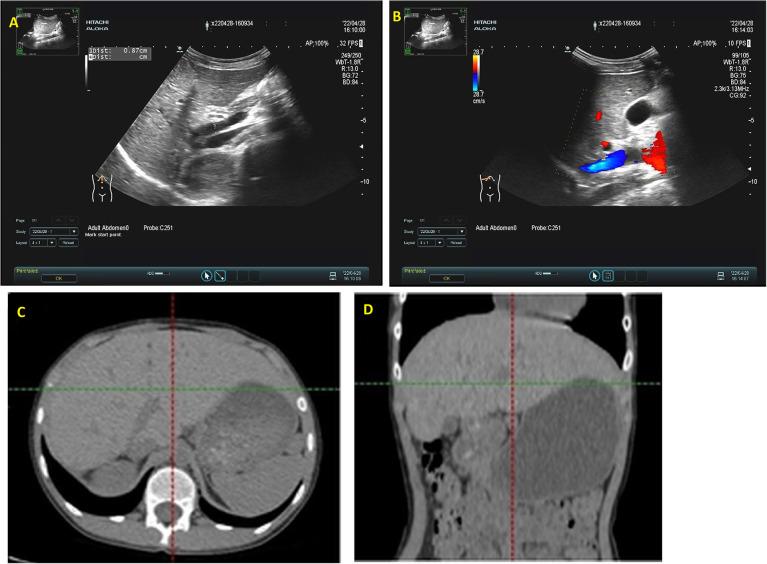

Case Report: Management of a congenital intrahepatic portosystemic shunt with portal vein aneurysm in a child using 3D computer-assisted partial right hepatectomy.

Congenital portosystemic shunts (CPSS) are rare pediatric vascular malformations characterized by abnormal development of the portal vein, which is attributed to incomplete embryonic remodeling of the hepatic and surrounding vasculature. CPSS manifests in two main forms: intrahepatic and extrahepatic. This study details the management of a pediatric patient diagnosed with Congenital Intrahepatic Portosystemic Shunt (CIPS) who was referred to our institution. By using a computer-assisted surgical system, the right hepatectomy was successfully performed, guided by precise intraoperative navigation based on three-dimensional reconstructions of enhanced CT imagery. The patient exhibited a favorable postoperative recovery trajectory, with the absence of complications or recurrence throughout the monitoring period.